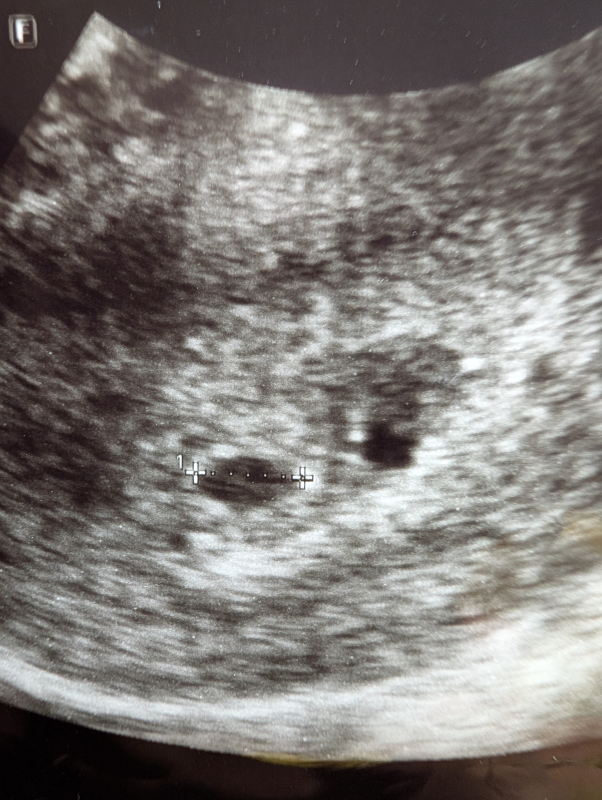

妊娠5週頃のエコー写真についてご相談です。

診察していただいた先生からは5mmで

順調に育っているとのお話のみでしたが

エコー写真を見返した際、測定した黒丸の右横にも

同じような黒丸がありこれはなんなのかと心配になりました。

妊娠初期のエコーで、黒い点が2つあったことがご心配なのですね。

胎嚢の近くにもう一つ黒い点が見られるのですね。実際にエコーを拝見していませんので、はっきりとしたことは明言できませんが、可能性として考えられるのは、出血のこともありますし、粘膜の塊などがそのように見えることもあります。また、おっしゃるように、双子の可能性もあると思います。

ですが、医師からは特に何も指摘がなかったということであれば、出血や双子ではない可能性が高いように思いますよ。粘膜の塊などが黒っぽく見えることもありますので、何も言われていないのであれば、そのようなものなのかもしれませんね。